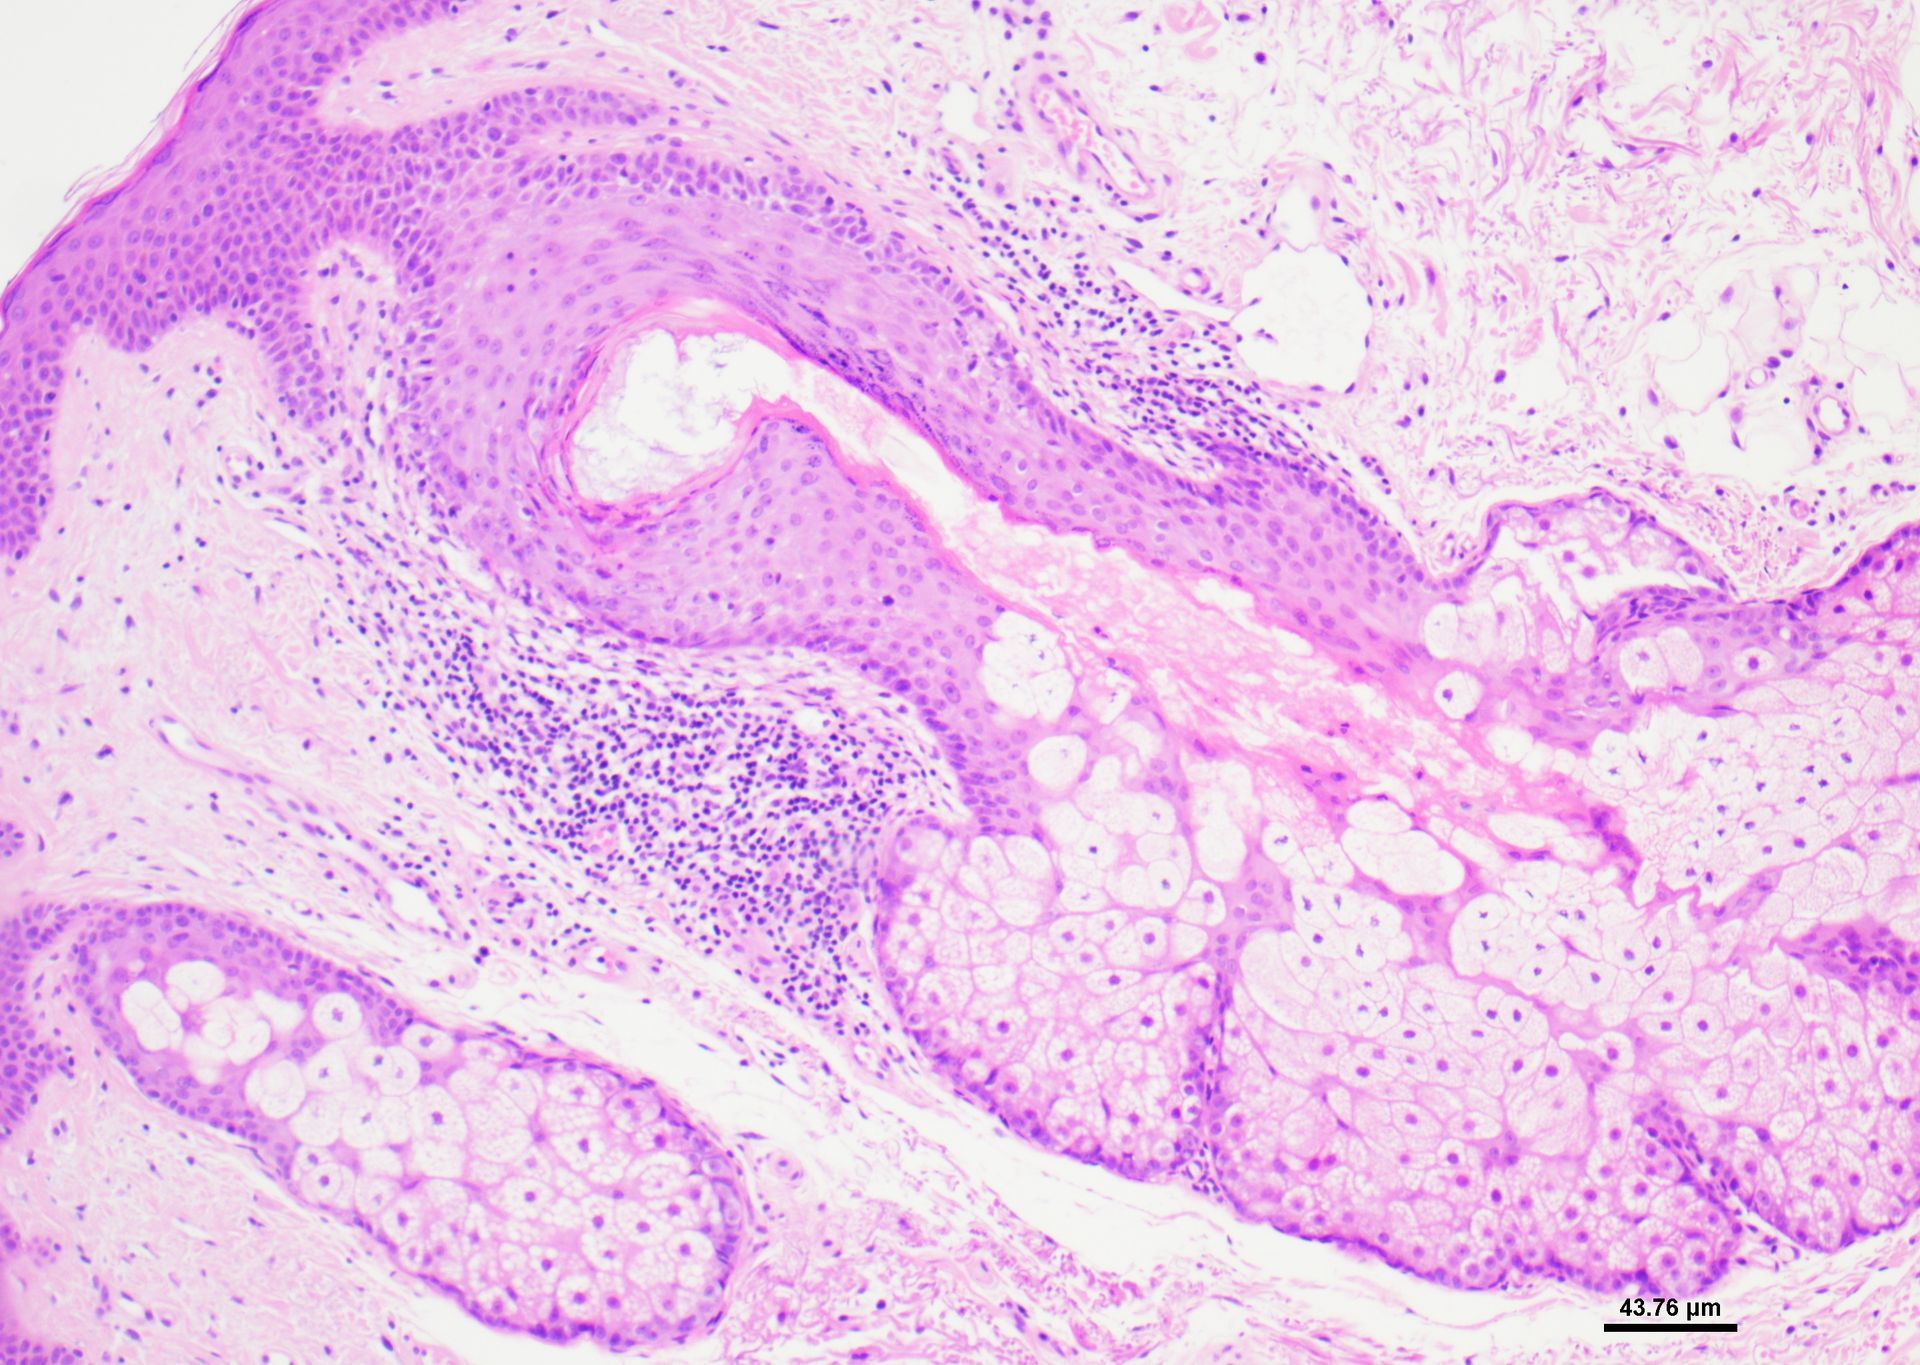

- Online na library ng mga larawang may kulay na nagpapakita ng pinakamainam at sub-optimal na paglamlam